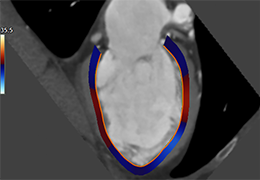

ANYTHINK 经导管主动脉瓣膜置换术分析系统